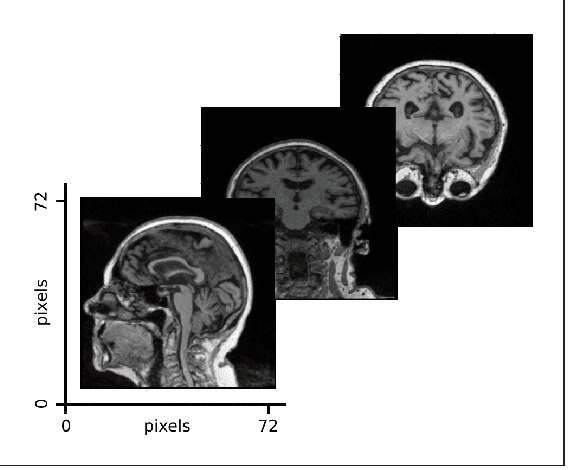

Abstract:Alzheimer's Disease (AD) is the most common neurodegenerative disorder with one of the most complex pathogeneses, making effective and clinically actionable decision support difficult. The objective of this study was to develop a novel multimodal deep learning framework to aid medical professionals in AD diagnosis. We present a Multimodal Alzheimer's Disease Diagnosis framework (MADDi) to accurately detect the presence of AD and mild cognitive impairment (MCI) from imaging, genetic, and clinical data. MADDi is novel in that we use cross-modal attention, which captures interactions between modalities - a method not previously explored in this domain. We perform multi-class classification, a challenging task considering the strong similarities between MCI and AD. We compare with previous state-of-the-art models, evaluate the importance of attention, and examine the contribution of each modality to the model's performance. MADDi classifies MCI, AD, and controls with 96.88% accuracy on a held-out test set. When examining the contribution of different attention schemes, we found that the combination of cross-modal attention with self-attention performed the best, and no attention layers in the model performed the worst, with a 7.9% difference in F1-Scores. Our experiments underlined the importance of structured clinical data to help machine learning models contextualize and interpret the remaining modalities. Extensive ablation studies showed that any multimodal mixture of input features without access to structured clinical information suffered marked performance losses. This study demonstrates the merit of combining multiple input modalities via cross-modal attention to deliver highly accurate AD diagnostic decision support.